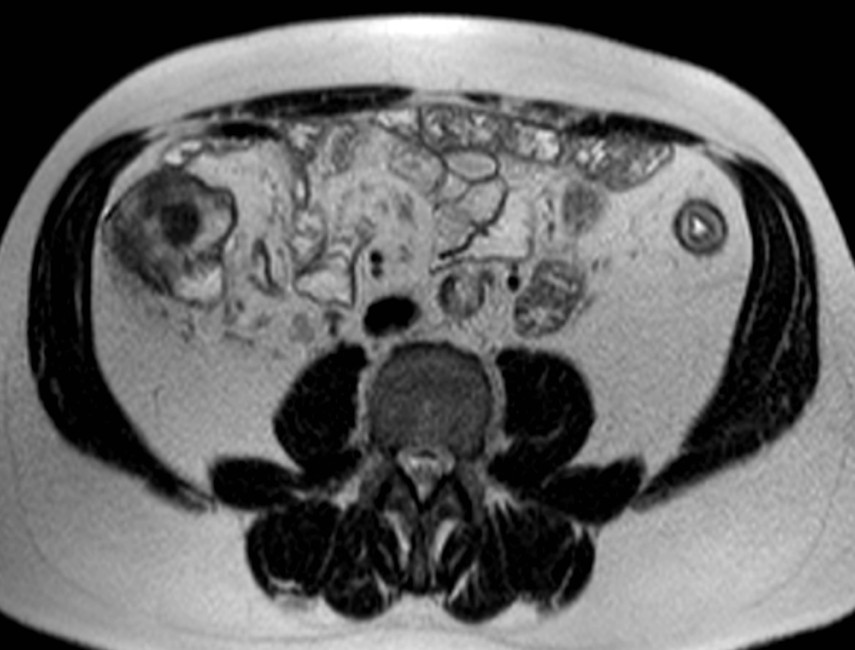

März 2017 von PD Dr. Peter Bannas aus Hamburg

Frage 1: Um welche Bildmodalität handelt es sich?

- a) MRT (native T2w-Sequenz sowie T1w-Sequenz mit Kontrastmittel)

- b) MRT (native T2w-Sequenz sowie native T1w-Sequenz)

- c) CT (portalvenöse und arterielle Phase)

- d) PET/CT (CT im Weichteilfenster und PET)

- e) CT (native und arterielle Phase)

Frage 2: Was führt in der benutzten Aufnahmetechnik am wenigsten wahrscheinlich zu Artefakten?

- a) Metallische Prothesen

- b) Luftansammlungen im Darm

- c) Bewegungen des Patienten während der Aufnahme

- d) Blutfluss

- e) Nierenzysten

Frage 3: Welche Struktur ist nicht erfasst?

- a) Colon descendens

- b) Colon ascendens

- c) Colon transversum

- d) Nieren

- e) Leber

Frage 4: Welcher Befund ist nicht vorhanden?

- a) Zielscheiben-Phänomen (Target-Sign)

- b) Ödem in der Submukosa

- c) Langstreckiger Verlust der Haustrierung

- d) Kontrastmittelanreicherung der Darmwand

- e) Pneumatosis intestinalis

Frage 5: Welche Diagnose stellen Sie?

- a) Colitis ulcerosa

- b) Colonkarzinom

- c) Lymphom

- d) Leiomyom

- e) Metastase

Preisfrage: Welche Erkrankung ist mit der Colitis Ulcerosa assoziiert?

- a) Primär biliäre Cholangitis

- b) Primär sklerosierende Cholangitis